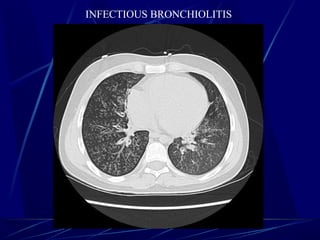

INFECTIOUS BRONCHIOLITIS

๏ถ Centrilobular nodules m/b further characterized by presence or

absence of โ€˜โ€˜tree-in-bud.โ€™โ€™

๏ถ Tree-in-bud -- Impaction of centrilobular bronchus with mucous,

pus, or fluid, resulting in dilation of the bronchus, with associated

peribronchiolar inflammation .

๏ถ Dilated, impacted bronchi produce Y- or V-shaped structures

๏ถ This finding is almost always seen with pulmonary infections.

Tree-in-bud

Tree-in-bud describes the appearance of an irregular and often nodular

branching structure, most easily identified in the lung periphery.

Typical Tree-in-bud appearance in a patient with active TB.